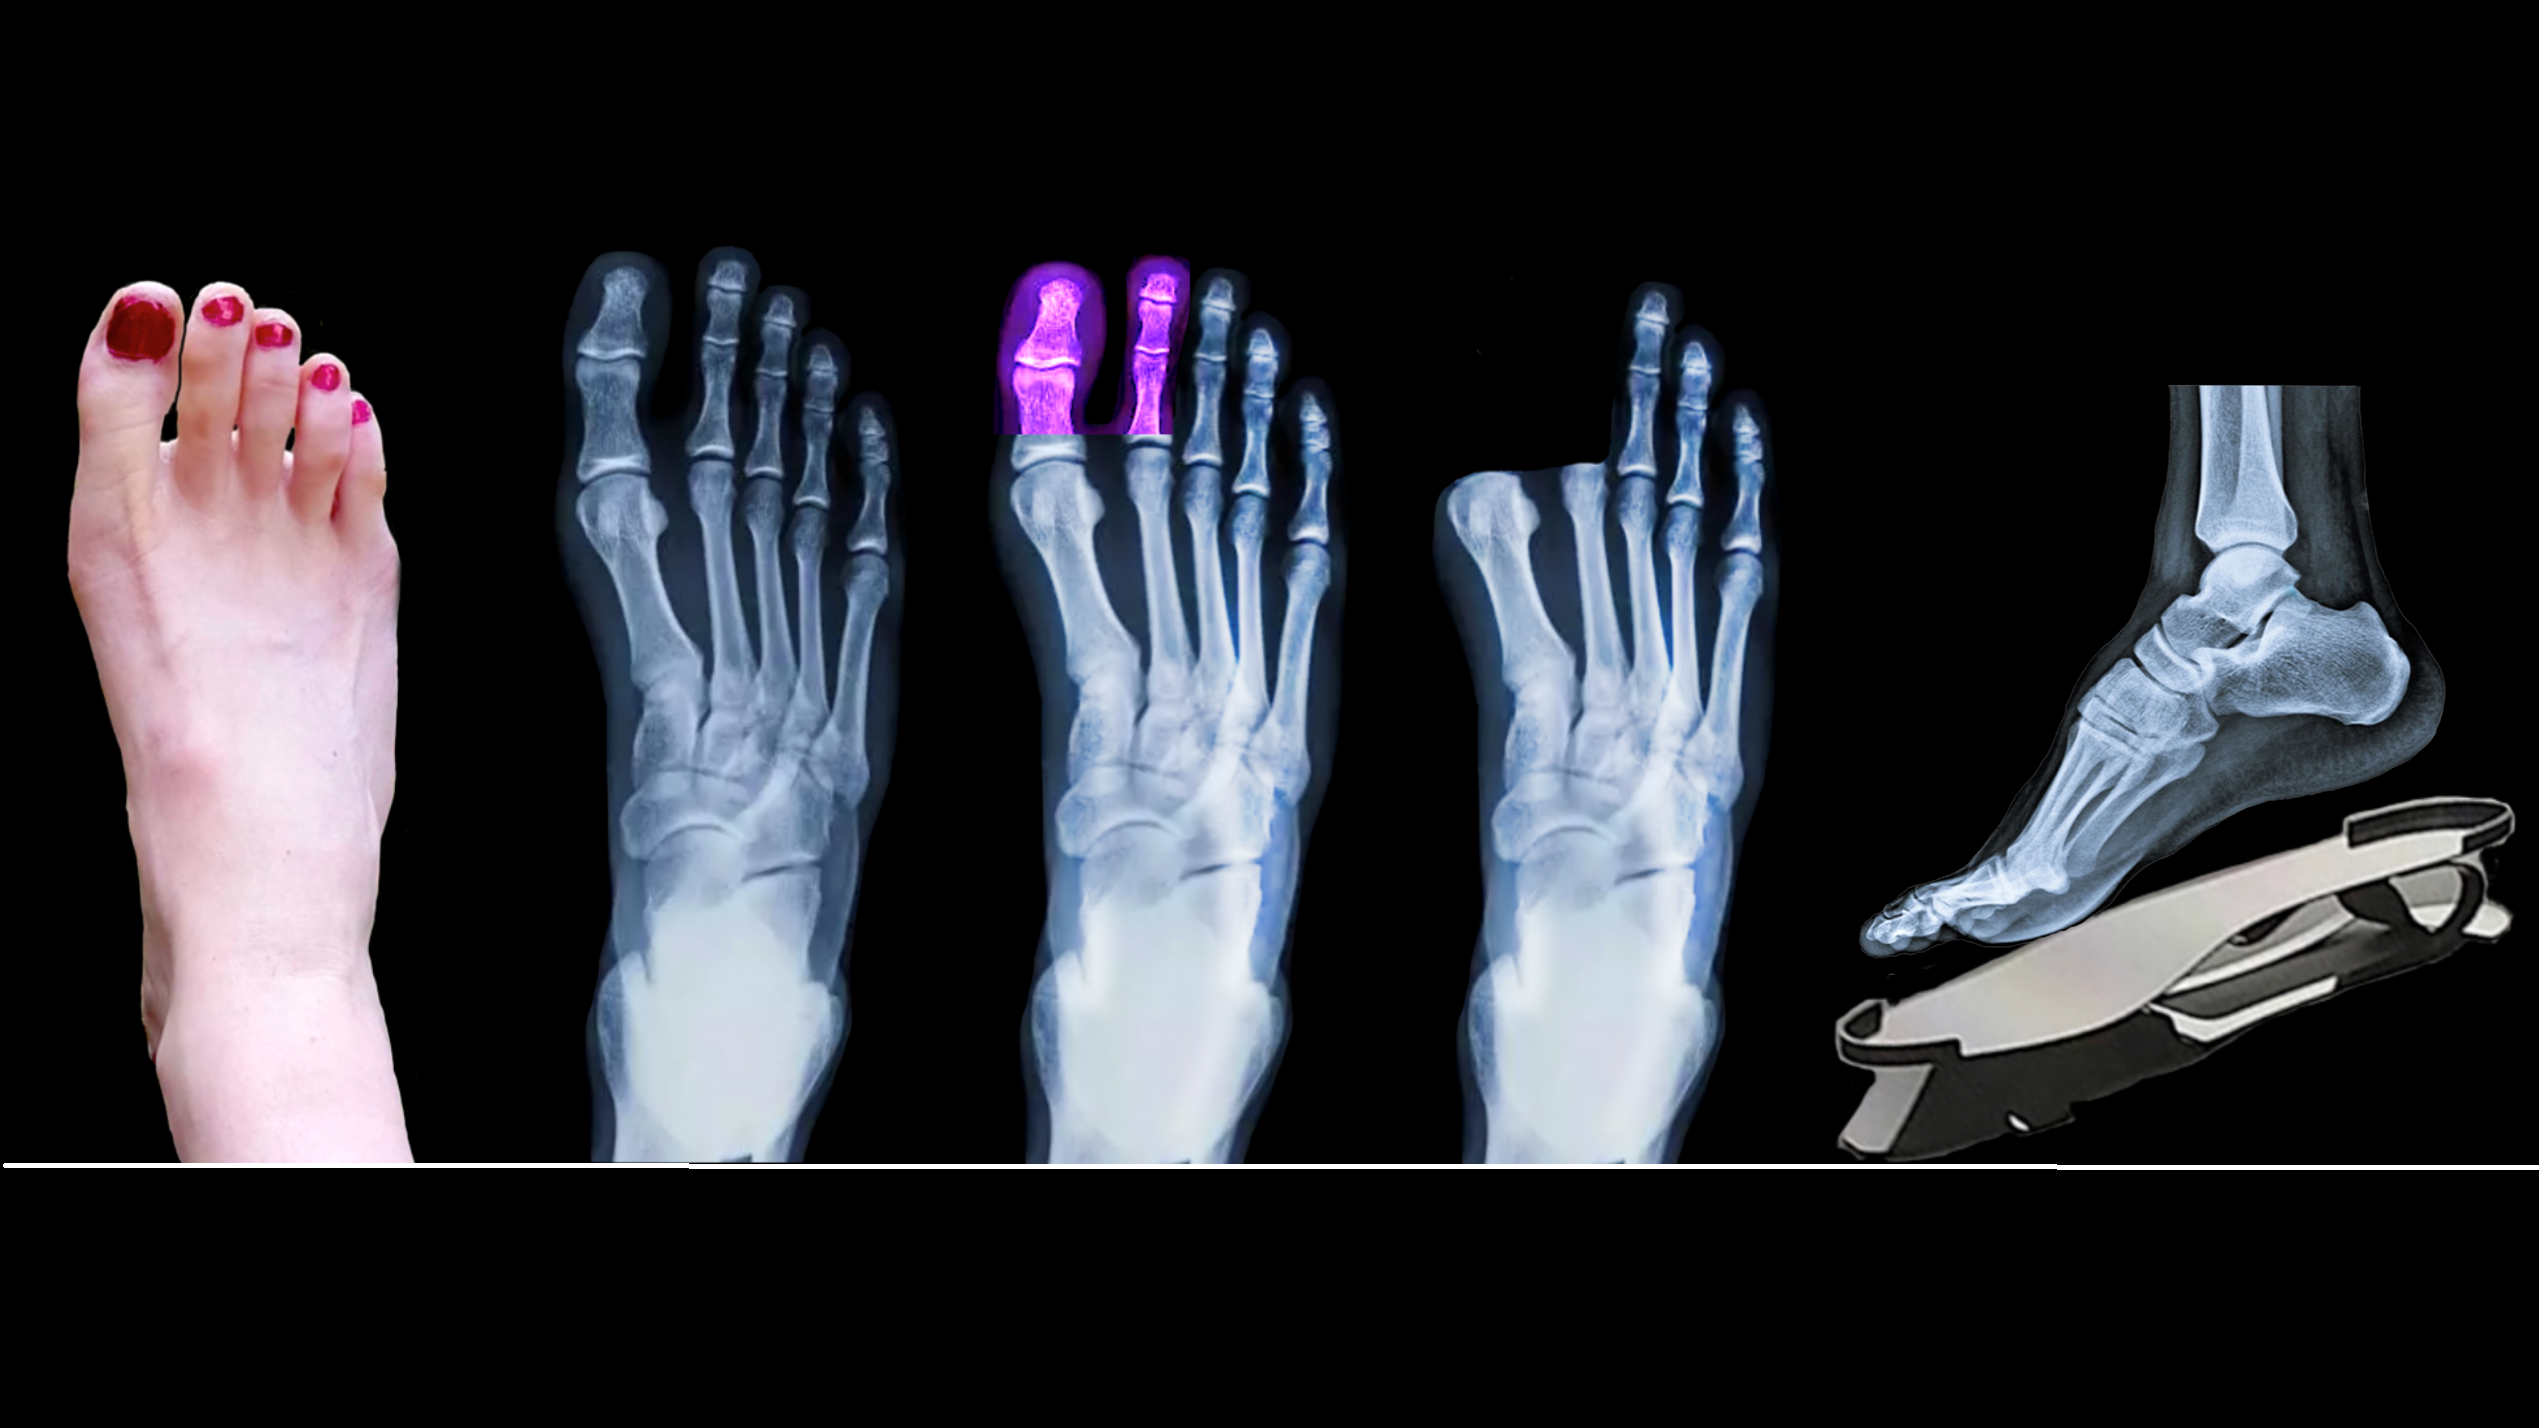

Bionic Walker – die Fußprothese der Zukunft

Das Projekt ‚Bionic Walker‘ versucht teilfußamputierten Menschen durch eine neuartige Fußprothese zu helfen. An ihrer Entwicklung ist unter anderem das Institut für Flugzeug- und Leichtbau der technischen Universität Braunschweig beteiligt.